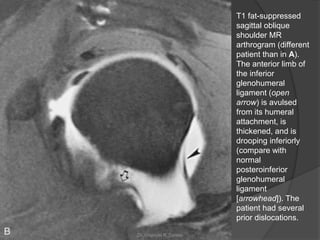

T1 fat-suppressed

sagittal oblique

shoulder MR

arthrogram (different

patient than in A).

The anterior limb of

the inferior

glenohumeral

ligament (open

arrow) is avulsed

from its humeral

attachment, is

thickened, and is

drooping inferiorly

(compare with

normal

posteroinferior

ligament

[arrowhead]). The

patient had several

prior dislocations.

T1 fat-suppressed sagittal oblique shoulderMR arthrogram (different patient than in A). The anterior limb of the inferior glenohumeral ligament (open arrow) is avulsed from its humeral attachment, is thickened, and is drooping inferiorly (compare with normal posteroinferior glenohumeral ligament [arrowhead]). The patient had several prior dislocations. Dr. Emanuel R. Dantas